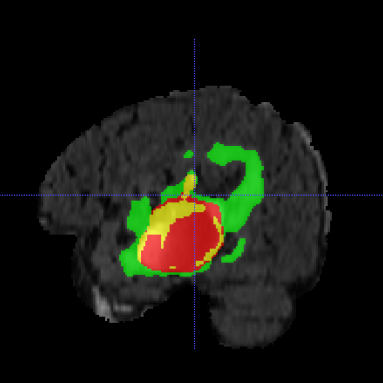

Multimodal Brain Tumor Segmentation Challenge (BraTS) aims to evaluate state-of-the-art methods for the segmentation of brain tumors by providing a 3D MRI dataset with ground truth tumor segmentation labels annotated by physicians [6, 11, 5, 3, 4]. This year, BraTS 2021 training dataset included 1251 cases, each with four 3D MRI modalities (T1, T1c, T2 and FLAIR) rigidly aligned, resampled to 1x1x1 mm isotropic resolution and skull-stripped. The input image size is 240x240x155. The data were collected from multiple institutions, using various MRI scanners. Annotations include 3 tumor subregions: the enhancing tumor, the peritumoral edema, and the necrotic and non-enhancing tumor core. The annotations were combined into 3 nested subregions: whole tumor (WT), tumor core (TC) and enhancing tumor (ET), as shown in Figure 1. Two additional datasets without the ground truth labels were provided for validation and testing. The validation dataset (219 cases) allowed multiple submissions and was designed for intermediate evaluations. The testing dataset (530 cases) will be analysed blindly using the docker submission, and is used to calculate the final challenge ranking.

Typically, the output result, even of a single model, is accurate as shown in Figure 1, however several cases still remain segmented imprecisely. Figure 2 shows an example of an incorrectly over-segmented whole tumor (WT) region, which is spilled over on the right side of the brain, most likely because the underlying MRI (Flair) has substantially higher intensity values in that region. More variability in training examples might have helped to solve the issue, or integration of anatomical knowledge of e.g. ”symmetrical highlights around ventricles are unlikely to be a tumor” , but such information is rather complicated to put inside of the network.